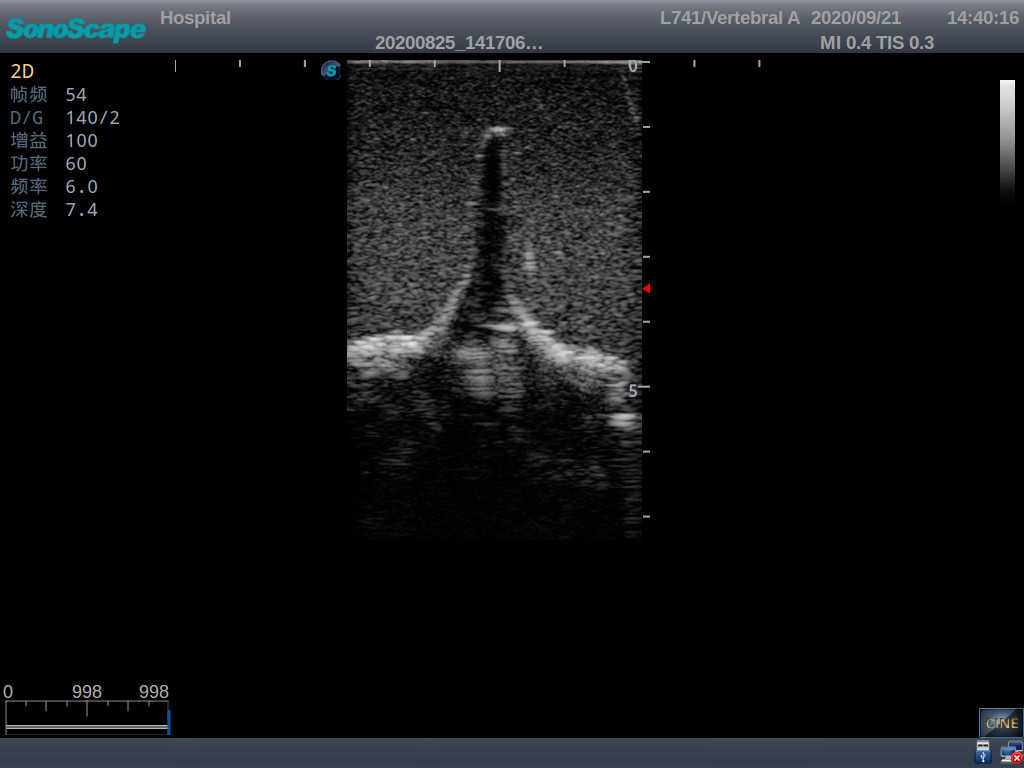

This model is an ideal choice for ultrasound-guided adult lumbar puncture training with true-to-life skin feel and touch, accurate anatomical structures as well as real clinical ultrasound images. Realistic resistance to needle tips and correct landmarks provide excellent hands-on experience.

2)  Real clinical ultrasound images